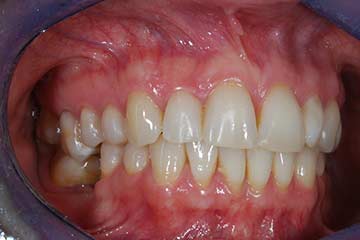

Riabilitazione gnatologica, ortodontica ed estetica

Durata del trattamento: un anno